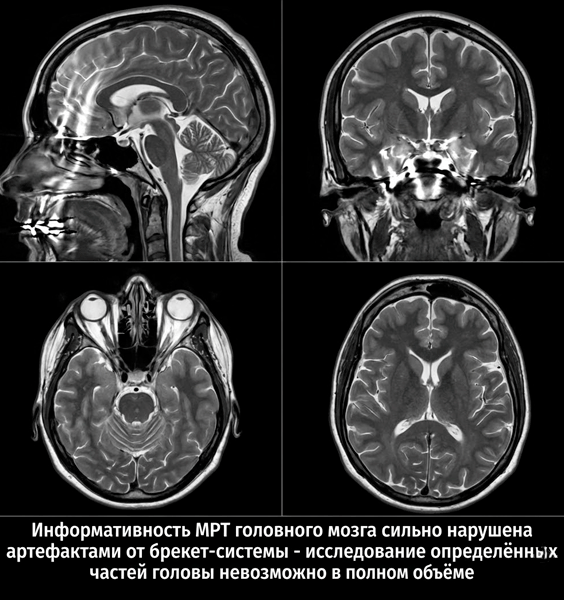

Багато людей задаються питанням, чи можна робити МРТ з брекетами? Ситуація подібна до коронок: слід консультуватися окремо у фахівців.